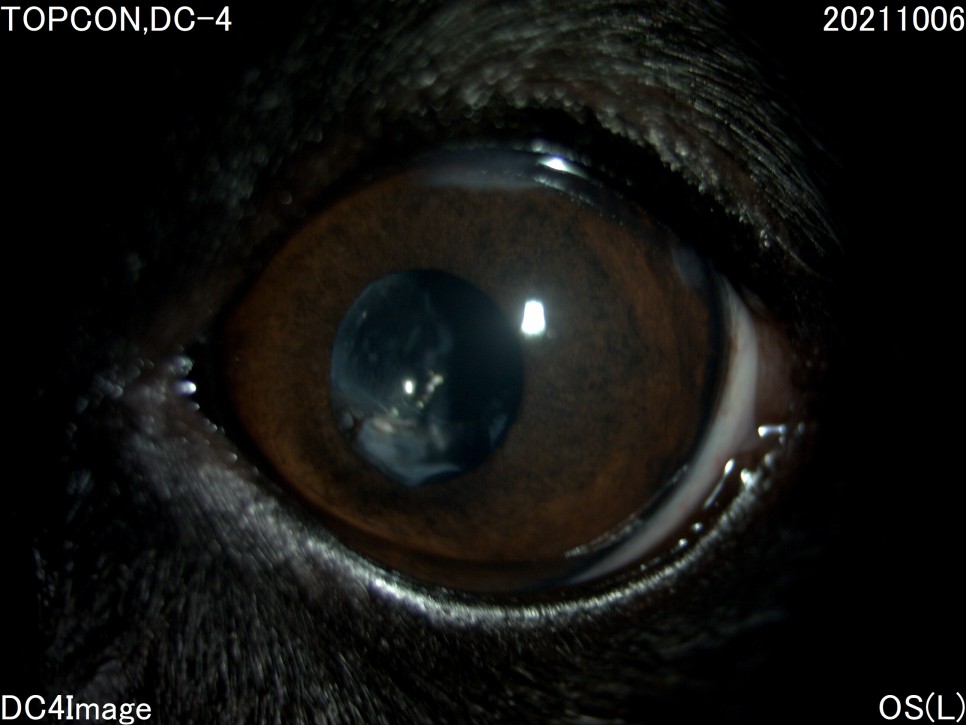

- 세극등 현미경 검사

양안의 백내장이 심하게 진행되고 있었지만 다행히도 당뇨병 관리를 하고 있는 전주 24시 동물병원은 당뇨병 관리 뿐만 아니라 눈 관리도 계속해 주셨기 때문에 내원 당시에는 양안 모두 심한 포도막염은 없었습니다.

그러나 왼쪽 눈은 백내장 단계 중 4기인 과성숙 단계로 진행되었으며, 이전에 앓고 있던 심한 포도막염에 의해 홍채의 일부가 수정체에 유착되어 있는 것이 보였습니다.

백내장이 오래 되거나 염증 반응이 심한 경우는 수정체를 감싸는 낭포 섬유화가 일어나 낭 자체에 백내장 파편이 붙어 있을 수 있는데, 자녀분이 바로 그런 상태였습니다.이런 경우 수술이 어려울 뿐만 아니라 수술 후 합병증의 발생률도 더욱 높아질 수 있습니다.

수술 일주일 후

수술 후 사진에 보이는 하얀 것은 무엇입니까?위의 사진상, 동공내에 보이는 흰 부분은 「후낭 백탁」이라고 하는 증상과 백내장에 의한 수정체 낭의 섬유화입니다.문자 그대로 백내장 수술 후 수정체의 후낭이라는 부분에 백탁 현상이 생기고, 이는 수정체 전낭 세포의 이주 등에 의해 발생합니다. 완성도는 아이에 따라 다르며, 개의 백내장 수술 후 80%이상에서 볼 수 있습니다.